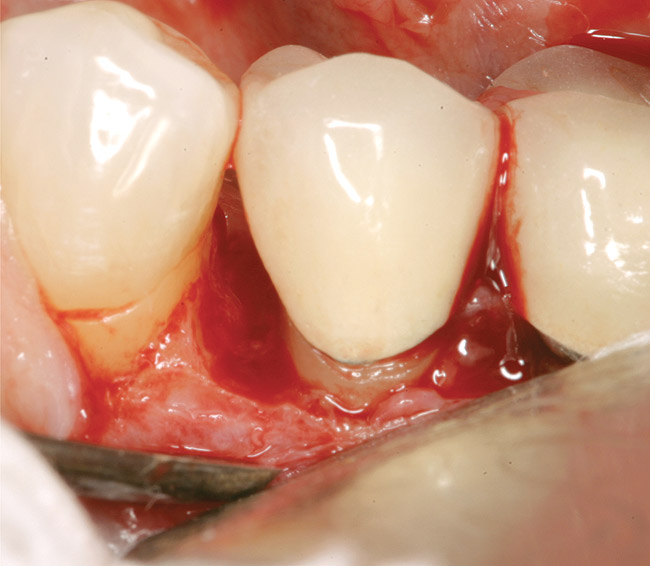

GTR, however, is still a viable option because there is consistency in published data—treating a vertical osseous lesion with this technique results in more clinical attachment gain than just open-flap debridement without performing GTR.46 The success rate in smokers, however, is significantly lower than in nonsmokers.47 Figure 11 and Figure 12] show a case in which tooth No. 22 had a large distal defect. Figure 13 shows the 6-year re-entry photograph, and Figure 14, the 6-year posttreatment radiograph, demonstrating complete clinical fill of the defect. Factors to consider in GTR include defect size (at least 3 mm to 4 mm), number of defect walls (at least two bony walls, but a three-wall defect is the most predictable to treat; Figure 15 shows a one wall defect, which is not graftable), furcation status (furcations are less predictable to obtain increased clinical attachment levels46), and mobility.48 However, patient compliance is critical in regard to both short-term and long-term success rates with GTR.

Figure 13  The case seen in Figure 11 on 6-year re-entry showing complete distal bone fill.

Figure 13